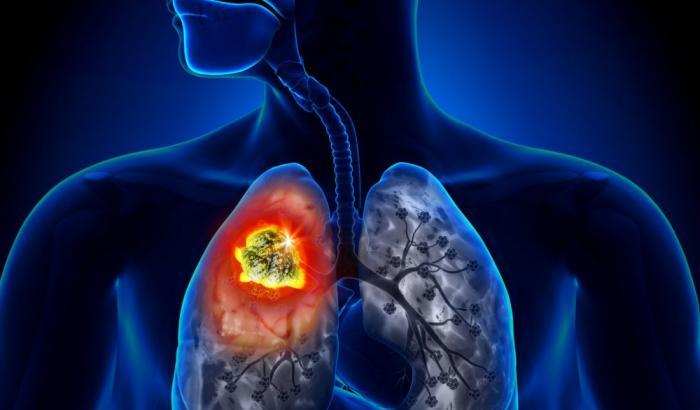

L’oggetto ha un costo contenuto, soli 1200 euro in tutto, ed è stato messo a punto dai ricercatori dell’Istituto Europeo di Oncologia con un finanziamento di 150 mila euro fornito dall’AIRC tre anni fa. Lo ha annunciato Lorenzo Spaggiari (Universita’ di Milano), Direttore della Chirurgia Toracica e responsabile del Programma Polmone IEO, precisando che l’obiettivo è quello di “dare scacco al tumore polmonare diagnosticandolo in tempo, quando le possibilità di guarigione possono raggiungere l’80%”.

I risultati dello studio su questi apparecchio – sviluppato in collaborazione con l’Universita’ Tor Vergata di Roma – sono stati pubblicati sul Journal of Breath Research. Su un totale di 146 individui, di cui 70 con diagnosi di tumore e 76 senza segnali di malattia, l’apparecchio e’ stato in grado di discriminare il respiro di chi si stava ammalando di tumore polmonare rispetto a chi non correva alcun rischio, con una precisione del 90%.